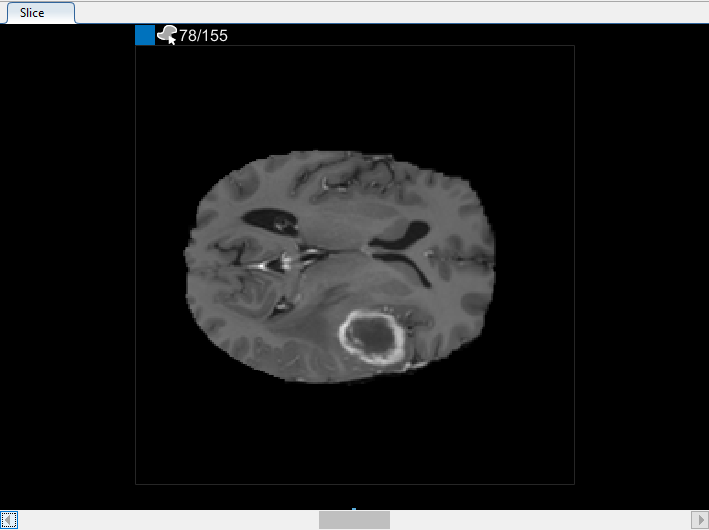

Можно также просмотреть каждый срез объема на панели « Срезе». Для перехода от среза к срезу используйте ползунок в нижней части панели. Вы можете увидеть опухоль на срезе 35 через срез 88. По умолчанию на панели « Срезе» отображается том, ориентированный вдоль оси X-Y, но изменить его можно с помощью кнопок в разделе Ориентация (Orientation) панели инструментов на вкладке Сегмент (Segmenter). Панель « Срез» также находится там, где для определения маски используются инструменты рисования.

На панели « Срезы» перейдите к срезу, где объект впервые появляется, и начните маркировать объект на каждом срезе с помощью инструмента рисования. На следующем рисунке этот пример использует инструмент Paint Brush для маркировки опухоли. Как и ранее, можно рисовать объект на каждом срезе, где он появляется, или использовать инструменты интерполяции, чтобы автоматически рисовать на нескольких срезах. После интерполяции можно использовать инструменты рисования, такие как ластик, для изменения автоматической сегментации на каждом срезе.